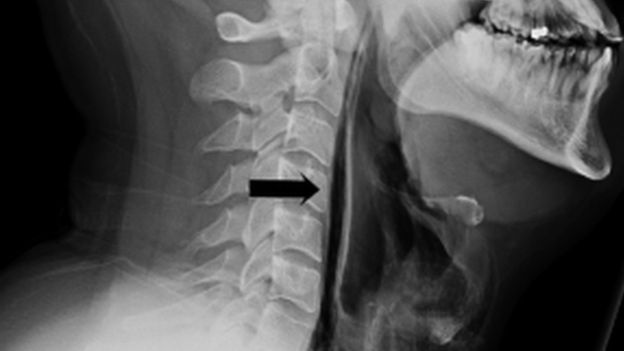

Aguantar o reprimir un estornudo puede tener serias consecuencias para la salud, tal fue el caso de un hombre sano de 34 años en Reino Unido que terminó siendo trasladado a urgencias con un agujero en la garganta.

El británico tapó su boca y nariz para intentar reprimir un estornudo fuerte, pero sintió un sonido extraño en su cuello e inmediatamente tuvo dolor junto con dificultades para hablar y tragar, pues perforó los tejidos al interior de su cuello, según reportó la revista British Medical.